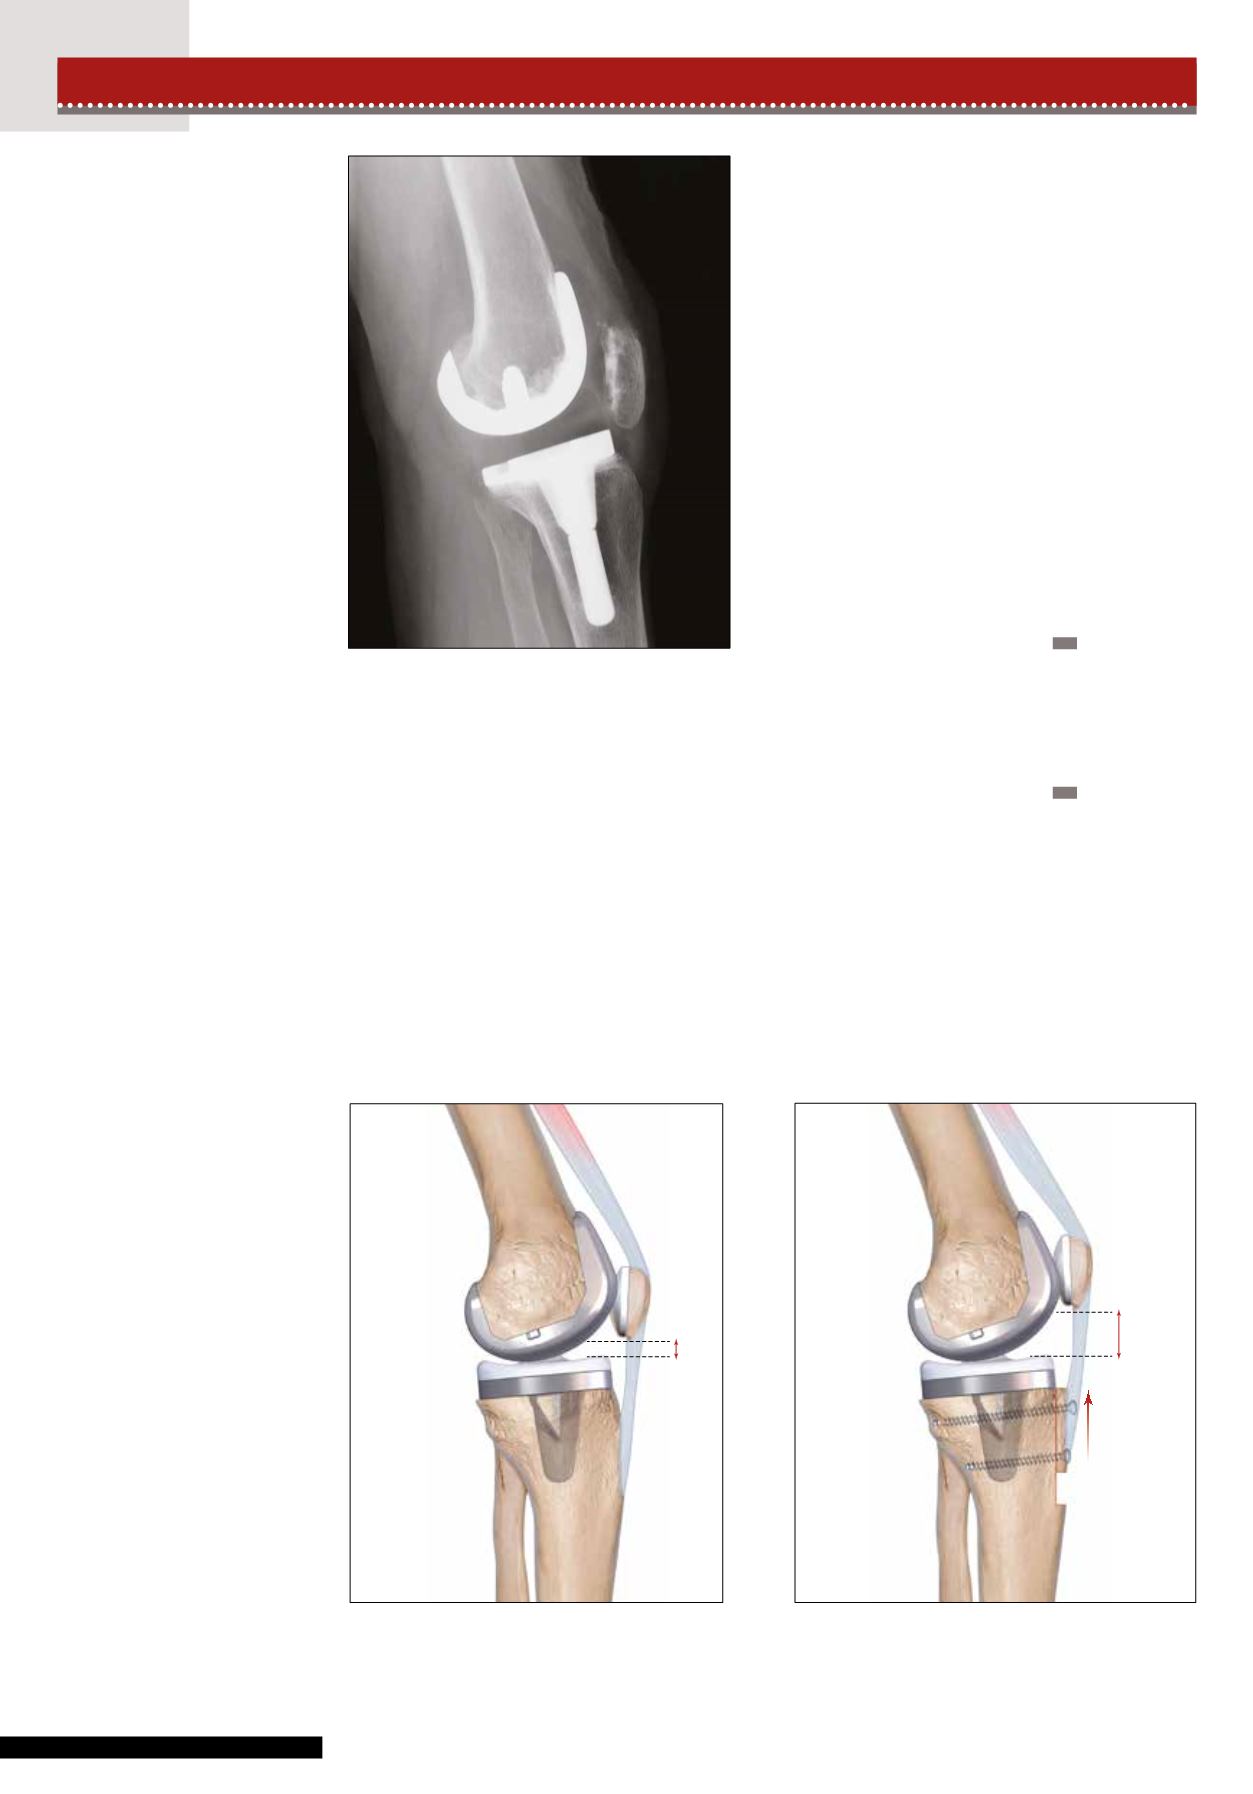

Figure 2 : Patelle Infera

sur PTG après algoneu-

rodystrophie. Le tendon

rotulien est très court

(1.8 cm maximum).

Figures 3 et 4 : Patella Infera sur PTG avec tendon rotulien de longueur suffisante (>2.5 cm). Ostéo-tomie de la TTA avec

transfert proximal de 1 cm. La baguette tibiale doit être suffisamment longue (6 cm). La fixation de la TTA est réalisée par deux vis

perpendiculaires, bicorticales, de diamètre 4,5 mm et de longueur suffisante. La partie haute de l’ostéotomie avec la réalisation d’une

coupe horizontale permet de résister aux forces d’arrachement.

1 cm

Figure 3

Figure 4